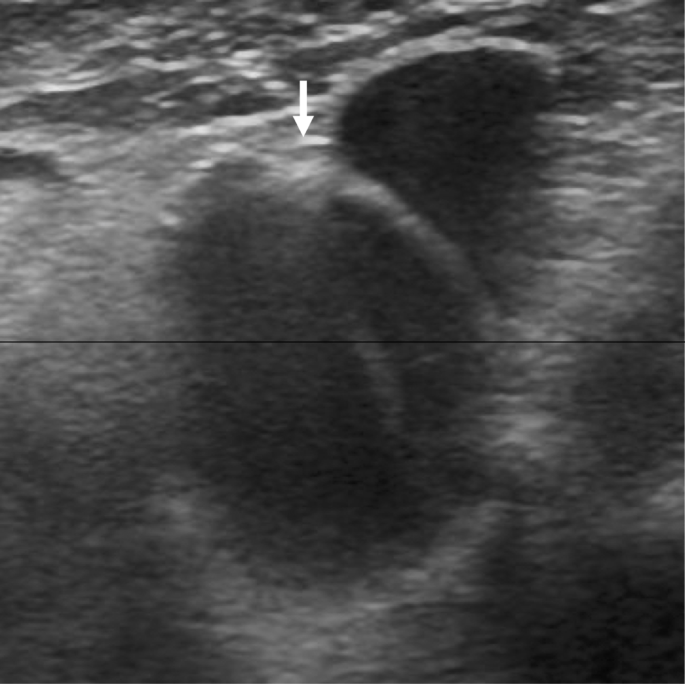

一名64岁的女性患者患有EGPA,并出现霍纳综合征(Horner syndrome)。她正在接受EGPA的糖皮质激素治疗以及心房颤动的抗凝治疗。超声检查显示颈总动脉和颈内动脉内存在内膜瓣和双腔结构。患者继续接受药物治疗,未发生缺血性中风,发病6个月后的随访显示霍纳综合征有所改善。超声检查未发现复发或动脉瘤形成,但颈动脉夹层是否完全愈合尚未得到确认。

一名64岁的女性患者因发现左眼视野异常而就诊。她有高血压、血脂异常、支气管哮喘、心房颤动、EGPA和胸主动脉夹层(TAD)以及白内障的病史。八年前,在调查多发性周围神经病变和中年发病的哮喘原因时,她发生了急性TAD并接受了紧急手术(主动脉移植)。随后被诊断为EGPA。她已经接受了14年的心房颤动抗凝治疗,并且也在接受EGPA的糖皮质激素治疗。眼科医生发现她的左眼视野异常,将其转诊至我们医院进行进一步检查。患者没有头痛、面部或颈部疼痛,也没有近期外伤史。体格检查显示她的左上眼睑轻度下垂(眼睑下垂),瞳孔缩小(瞳孔缩小,即霍纳综合征)。超声检查未发现复发或动脉瘤形成,但颈动脉夹层是否完全愈合尚未得到确认。

一名64岁的女性患者因约三周前发现左眼视野异常而就诊。她有高血压、血脂异常、支气管哮喘、心房颤动、EGPA和胸主动脉夹层(TAD)以及白内障的病史。八年前,在调查多发性周围神经病变和中年发病的哮喘原因时,她发生了急性TAD并接受了紧急手术(主动脉移植)。随后被诊断为EGPA。她已经接受了14年的心房颤动抗凝治疗,并且也在接受EGPA的糖皮质激素治疗。眼科医生发现她的左眼视野异常,将其转诊至我们医院进行进一步检查。患者没有头痛、面部或颈部疼痛,也没有近期外伤史。体格检查显示她的左上眼睑轻度下垂(眼睑下垂),瞳孔缩小(即霍纳综合征)。超声检查未发现复发或动脉瘤形成,但颈动脉夹层是否完全愈合尚未得到确认。